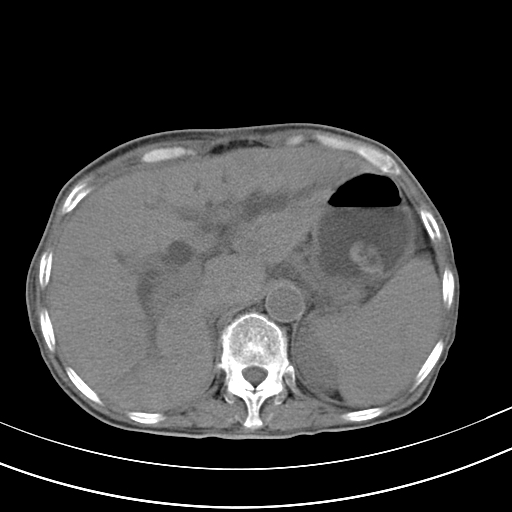

病人上腹部胀痛拌全身黄染八天

结石好象不明显吧?胆管稍扩张。

右侧少量胸水,胆囊增大,肝内胆管扩张,肝门部结构杂乱,建议增强。

考虑胰头癌或胰腺炎

肝内胆管及胰管扩张考虑为胰头区占位,肝门淋巴结增多,肝内多发低密度影,考虑为转移。门脉高压,脾大,胆囊大。

肝内胆管及胰管扩张,胰头增大考虑为胰头区占位,肝门淋巴结增多,考虑为转移。建议增强,脾大,胆囊大,壁厚,慢性胆囊炎。胃壁好像也增厚,且有一肿物。

胆囊增大,肝管扩张

脾大,

腹水,右胸腔少量积液。

胰腺炎。

1)考虑胰头癌并胆系低位梗阻;建议行ct增强扫描检查。2)慢性胆囊炎。3)脾大。4)少量腹水。5)双侧少量胸腔积液。